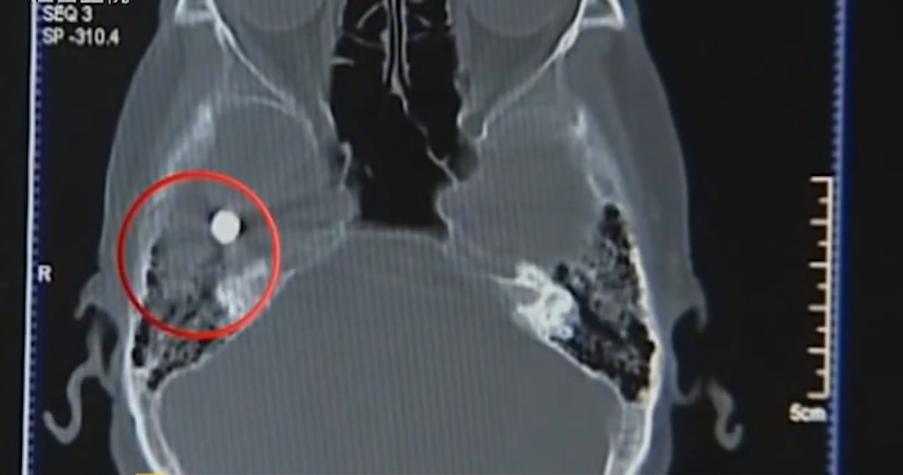

在检查刚开始,机器设备就检测到,在老太太脑部区域有一块高密度的小黑块。

图片非常清晰,那一小块阴影在整个图片中,异常显眼。

按理说就算有脑瘤,检查的结果也不会是这个样子的。

在场的医生以为是老太太头上的发卡没有摘掉,但是检查后,老太太却并没有带发卡。

但是画面中的黑块还是显示在那个区域,医生怀疑是设备的原因,但是在检查过后,机器没有任何问题。

看来,这黑块就是在老太太脑袋里,恐怕金广英最近头痛的原因,应该就是因为这个神秘的东西在作怪了。

原来,经过多次的扫描,发现这是一个柱状的物体,在图像上,又是一个条状的影子。结合两种情况。

最终确定,这是一个圆柱体,并且有一头还是尖的。当时医生就有个想法,这个金属物体,是颗*弹子**!